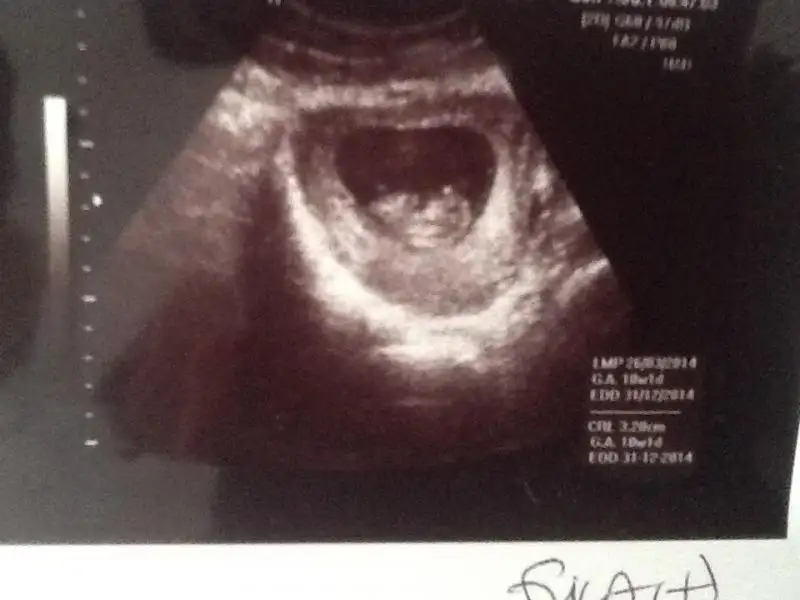

Bu ucuncu oldugu icin artik deneyimliyim tabi hemen anladim ve bir test aldim cikacagindan cok emindim esim bile yok canim demisti gorunce o da sasirdi :) dr a gittigimde daha kese bile yoktu kan tahlilinden ogrendik bugun itibari ile tam 11+2 yiz allah isteyen herkese versin insallah